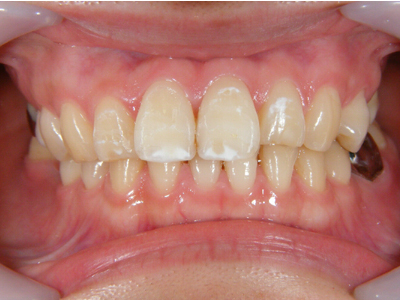

5. 施術前正面観

この患者様に関しての口腔内写真は、この段階から撮らせていただきました。初診時に撮っていれば良かったと痛感しています。